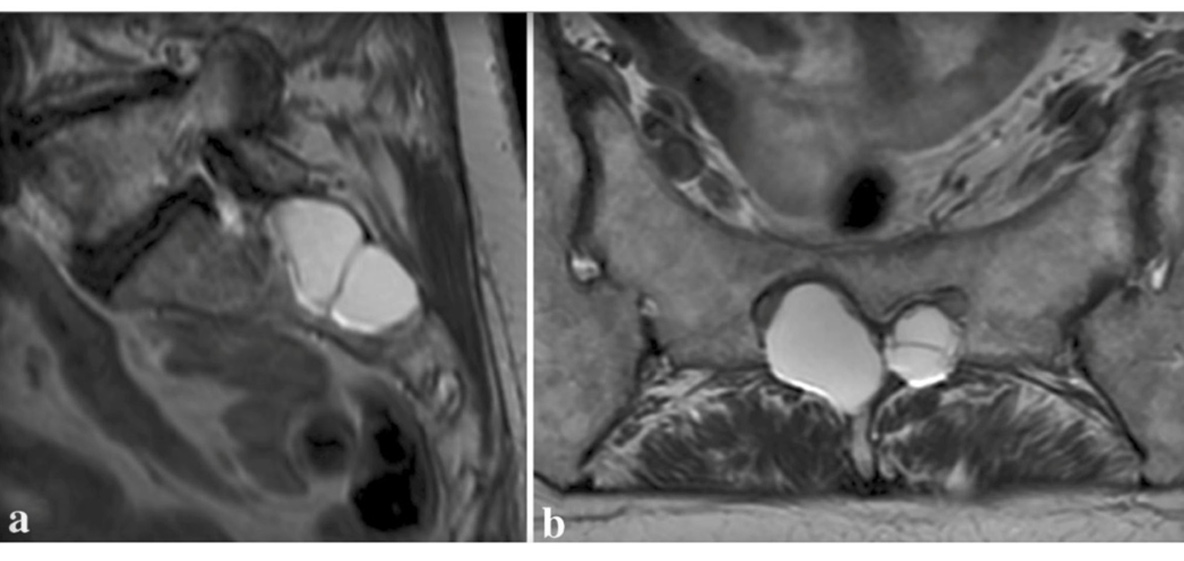

Figura 2. (a) Exploraciones sagitales y (b) axiales de resonancia magnética que muestran múltiples quistes de Tarlov en el nivel sacro S2 que causan erosión ósea.

Se piensa que los QT son un hallazgo radiológico común, frecuentemente asintomático, de forma que en ausencia de síntomas, o incluso mínimamente sintomático, puede quedar sin informar por el radiólogo, o no ser considerado por el médico que pidió la prueba4,5. Si el quiste ha estado presente durante años puede aparecer erosión y remodelación del hueso sacro u otras vértebras de la columna4. En determinadas condiciones, los quistes se llenan con más LCR comprimiendo importantes fibras nerviosas lo que origina una variedad de síntomas que incluyen el dolor crónico4.